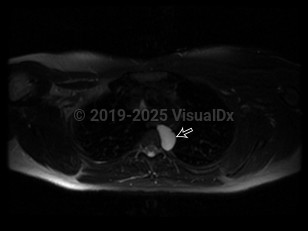

Imaging Studies image of Bronchogenic cyst - imageId=6831484. Click to open in gallery.  caption: '<span>Axial MRI image of the chest demonstrates a circumscribed lesion in the left posterior  mediastinum which is intermediate in intensity on T1 and hyperintense on  T2 consistent with a proteinaceous cyst (straight black arrow).</span>'

Axial MRI image of the chest demonstrates a circumscribed lesion in the left posterior mediastinum which is intermediate in intensity on T1 and hyperintense on T2 consistent with a proteinaceous cyst (straight black arrow).